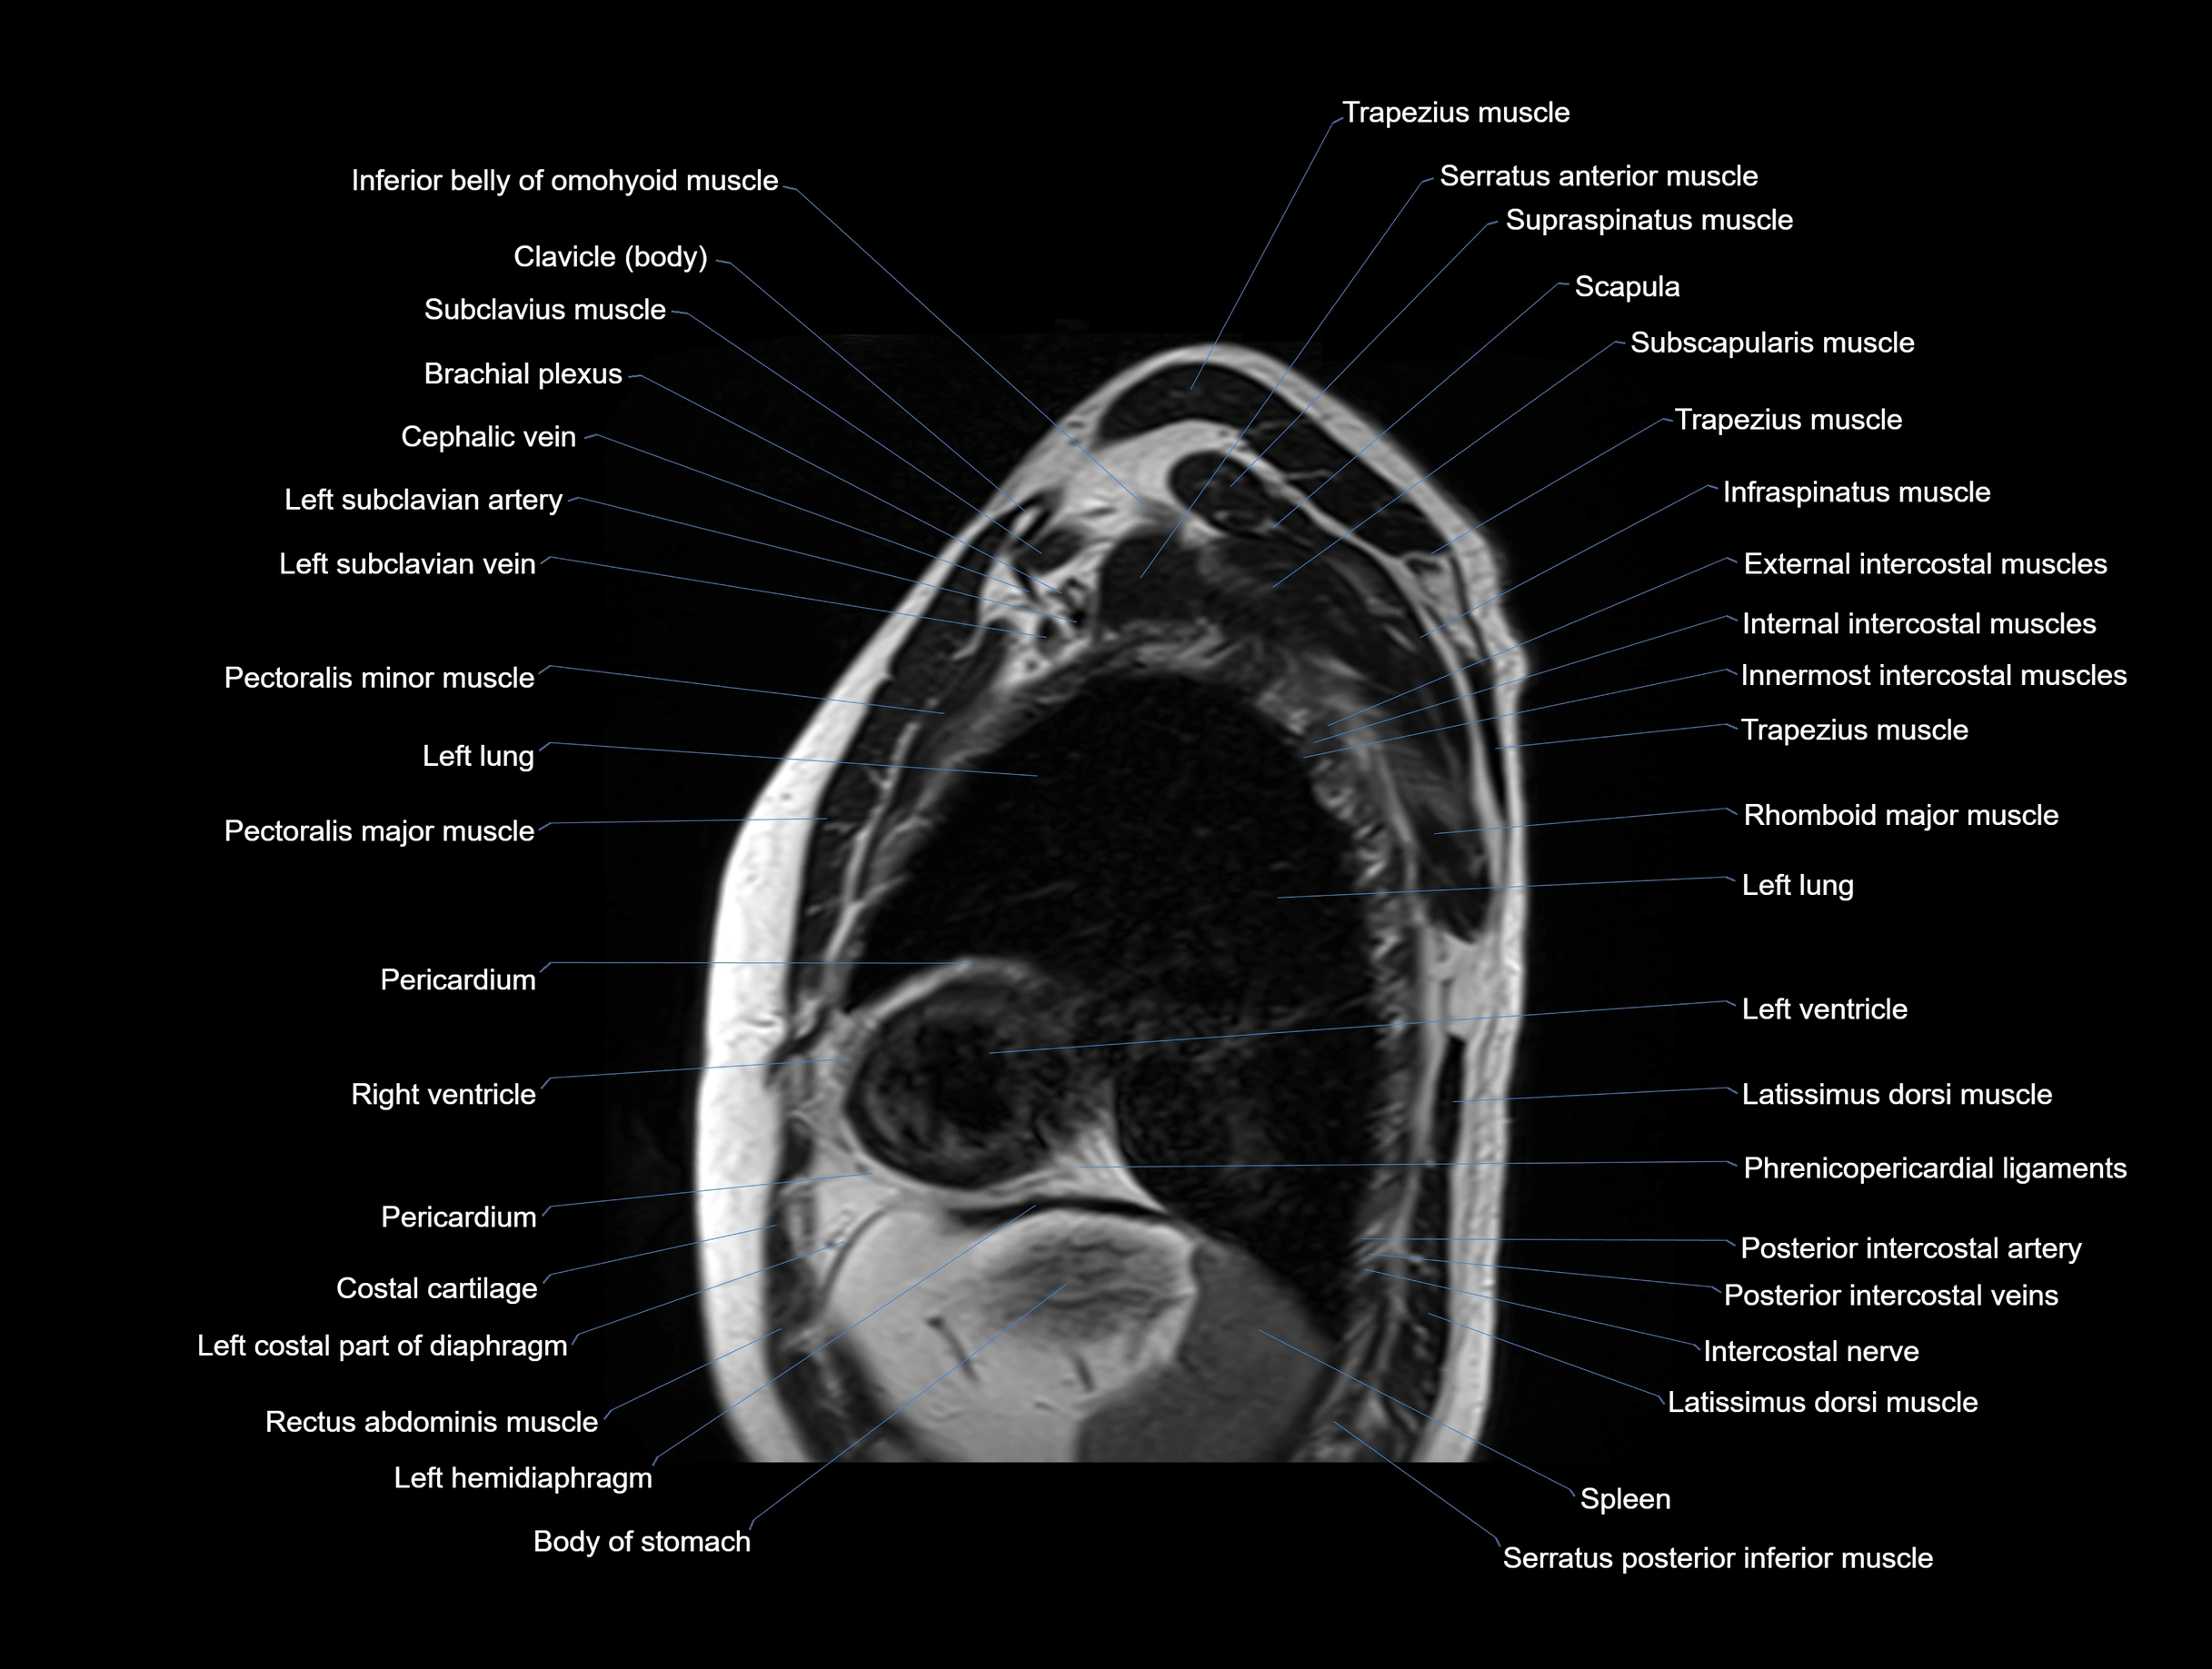

MRI images